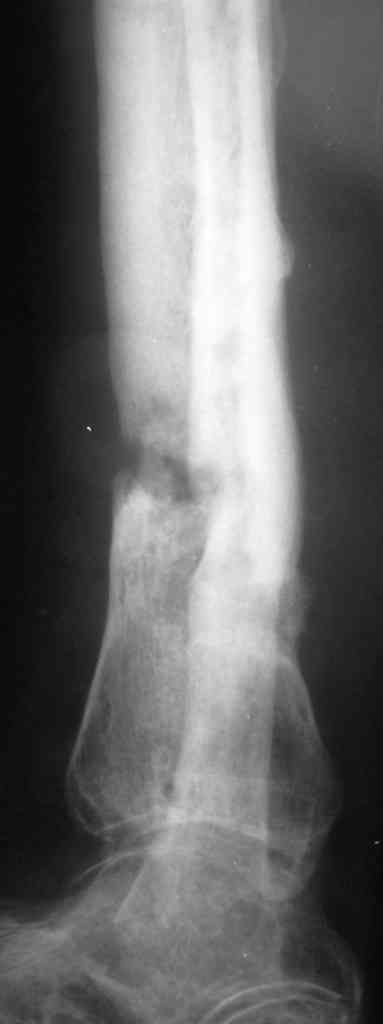

Коротко анамнез: травма в 2004 г. - открытый оскольчатый перелом н/3 голени, имелась рана 4х5 см. по передне-внутренней поверхности. Заживление раны вторичным натяжением. Сращения в АВФ нет. В 2005 г. в нашей клинике произведена костная свободная аутопластика с наложением АВФ. В послеоперационном периоде некроз в области старого рубца 2х3 см., тогда же произведена кожная аутопластика на питающей ножке. Сращения в течение 6 мес. нет, аппарат снят.

В 2006 г. произведена костная аутопластика на сосудистой ножке, иммобилизация гипсовой повязкой. На данный момент признаков консолидации нет.

Периодически у пациента возникают явления дерматита на применение местно лекарственных препаратов на голени, периодически открывается точечный свищ по передней пповерхности в проекции ложного сустава с серозно-гнойным отделянмым.

Укорочение конечности на 4,5-5,0 см., растройств чувствительности нет. При ходьбе конечность нагружает практически полностью при использовании тутора и ортопедической обуви. Внешний вид и R-гр. на фото. У больного еще пока сохранился настрой на лечение.

У меня в мыслях в первую очередь удлинить конечность. В области ложного сустава вмешиваться страшно из-за плохой кожи. Какие будут мысли?